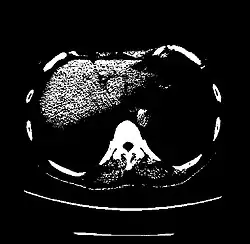

The Hounsfield scale (/ˈhaʊnzfiːld/ HOWNZ-feeld), named after Sir Godfrey Hounsfield, is a quantitative scale for describing radiodensity. It is frequently used in CT scans, where its value is also termed CT number.

| Kidney | +20 to +45[8] | |

| Liver | 60 ± 6[26] | |

A practical application of this is in evaluation of tumors, where, for example, an adrenal tumor with a radiodensity of less than 10 HU is rather fatty in composition and almost certainly a benign adrenal adenoma.[31]